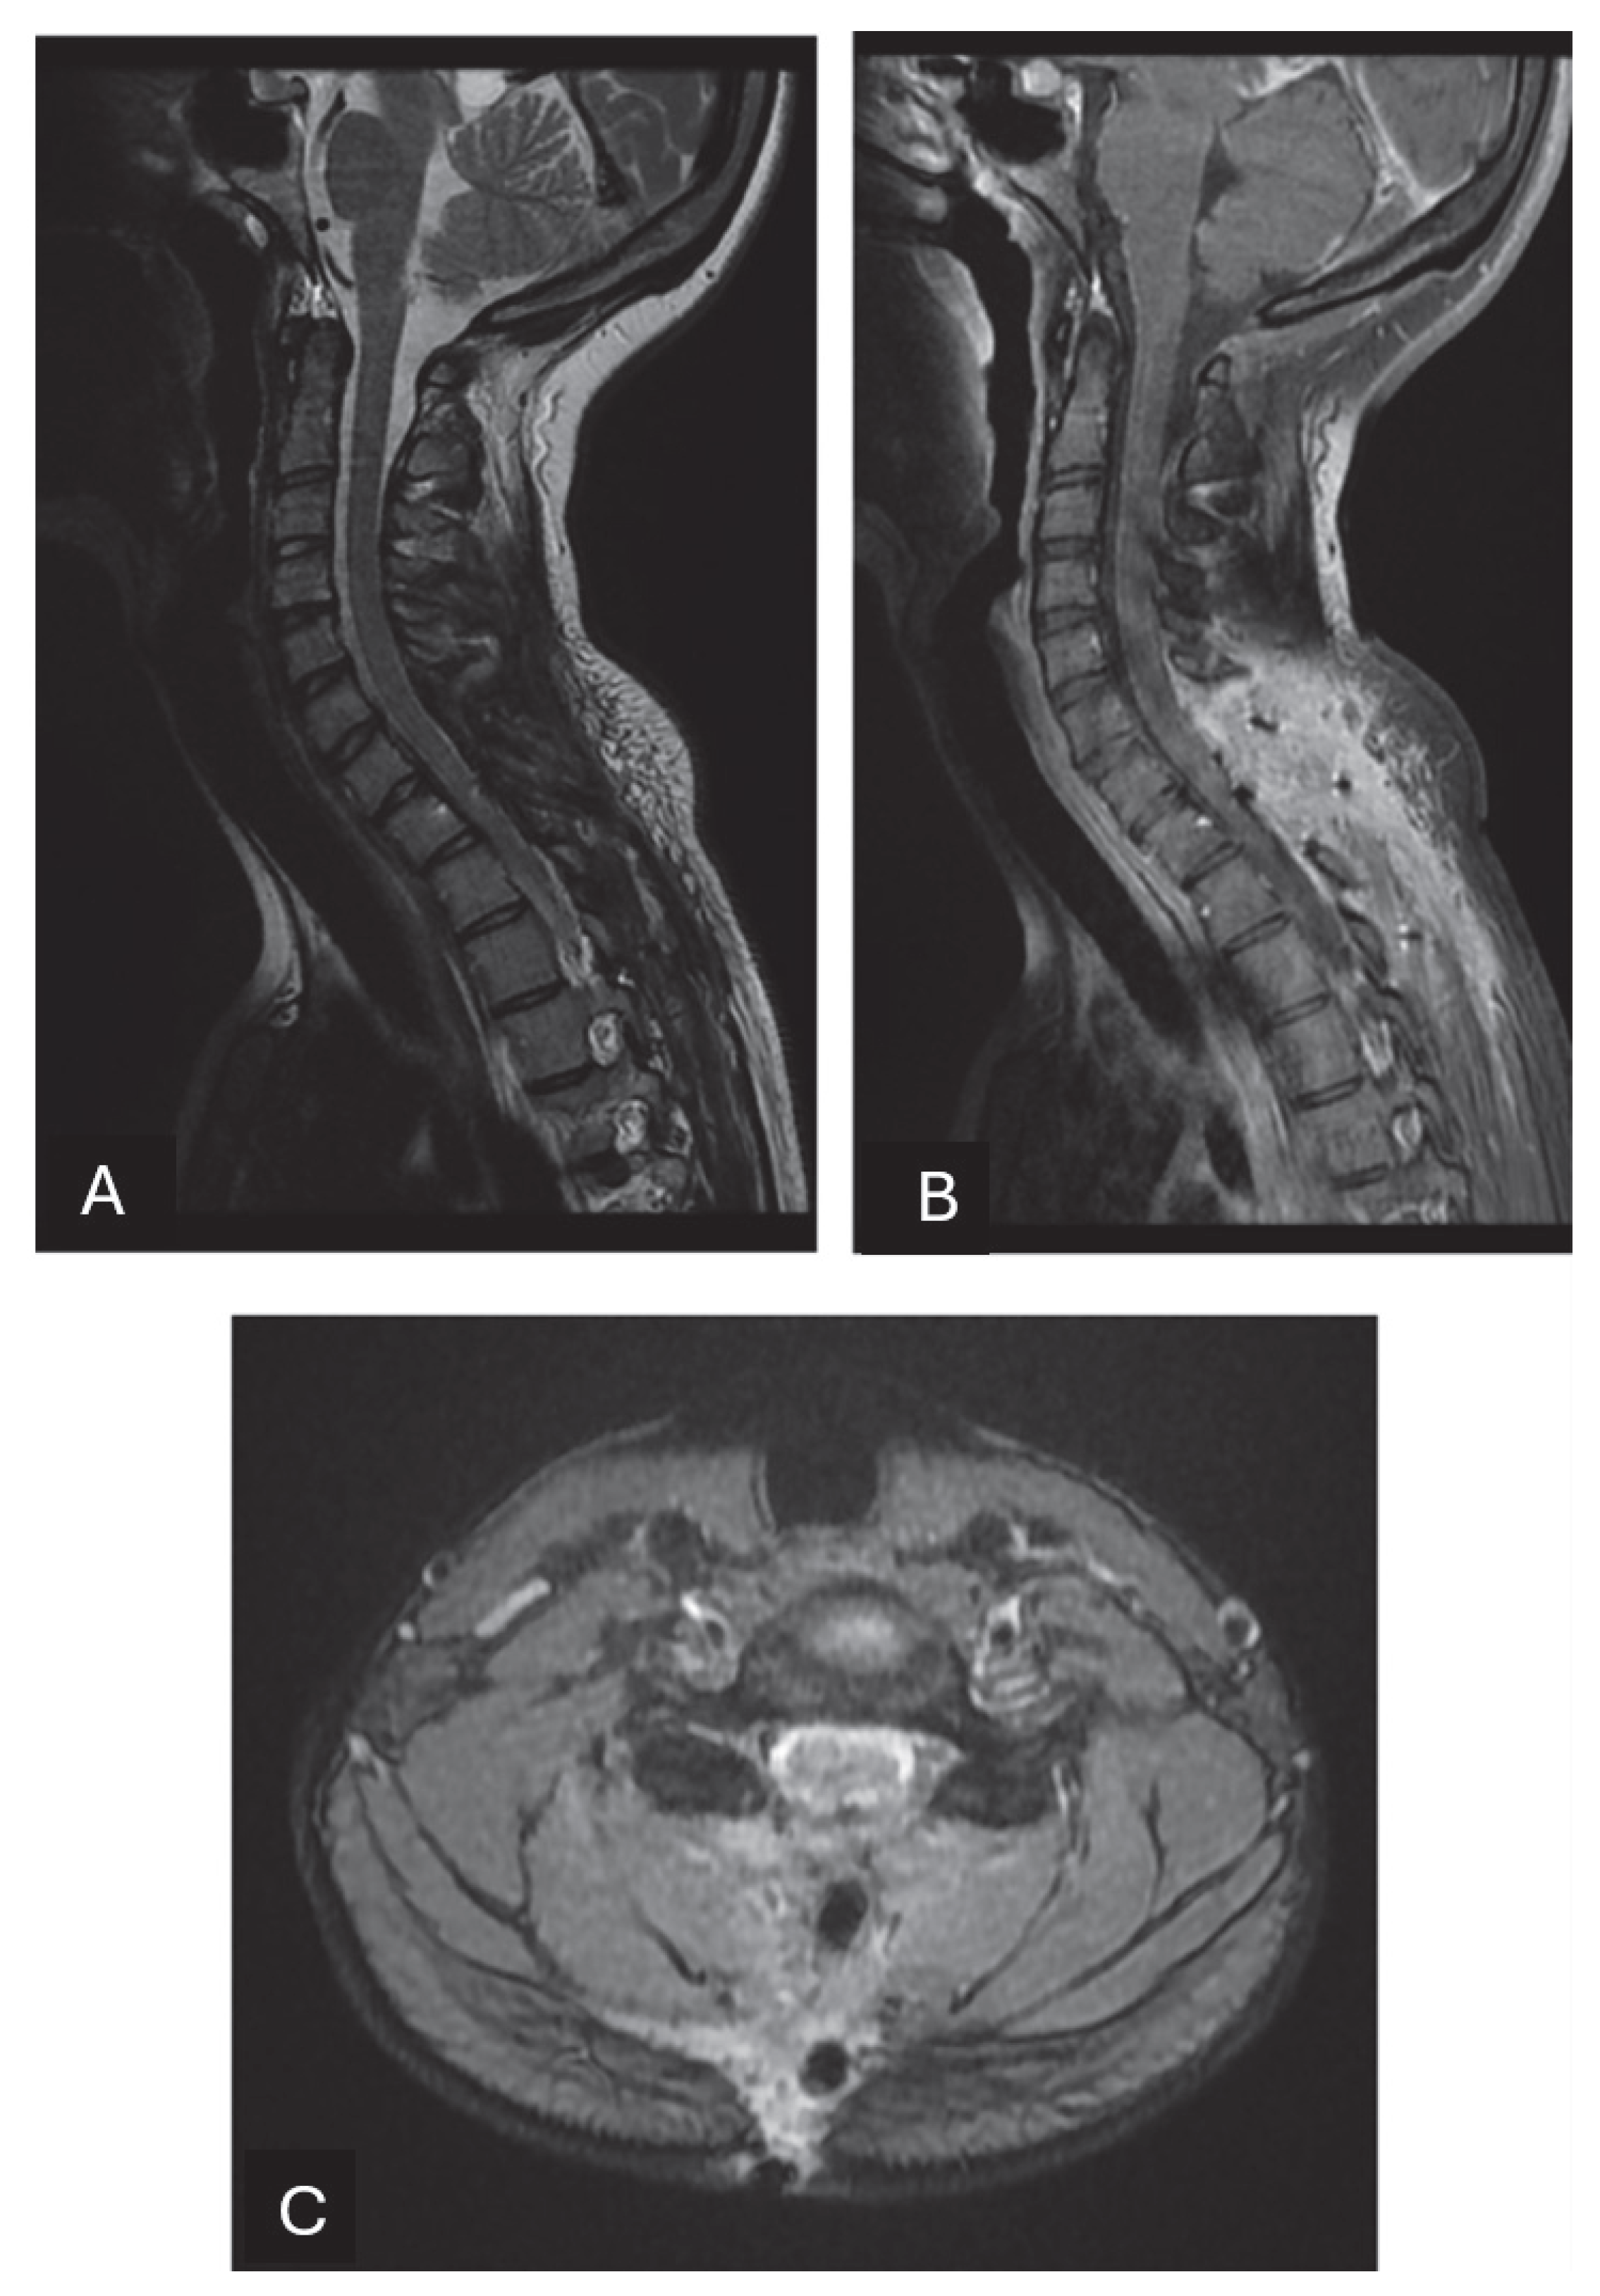

2. Case Presentation

| Present case | 1 | F | 15 | C7-T1 | Intradural Extramedullary | Lower limb hypoesthesia and weakness, mild urinary incontinence | GTR No RT | No | 16 |